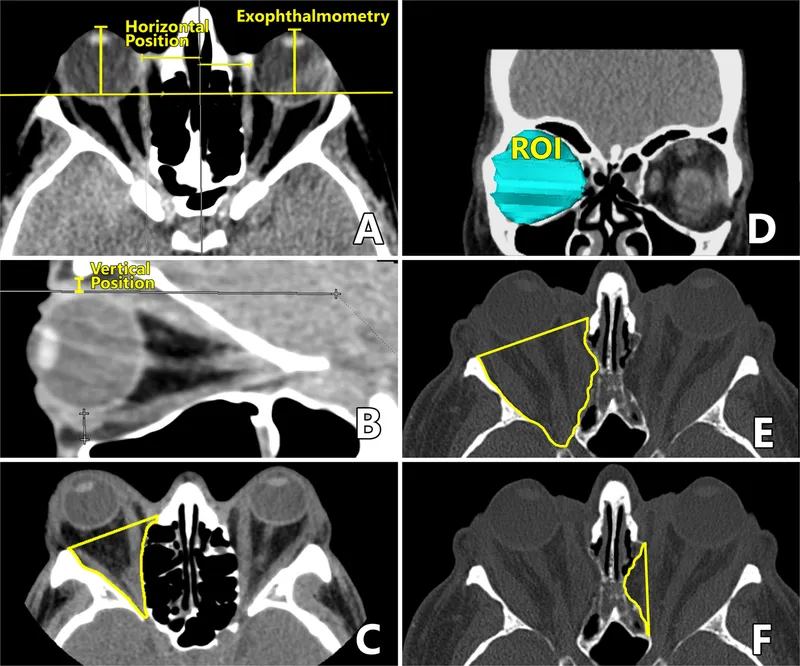

| Clinical Finding | Measurement | Significance | Differential Diagnosis | Urgency Level |

| Proptosis >25mm | Hertel exophthalmometry | Severe space-occupying lesion | Tumor, abscess, hemorrhage | High |

| Vision <20/40 | Snellen chart | Optic nerve compromise | CON, AION, tumor | High |

| IOP >30mmHg | Goldmann tonometry | Orbital compartment syndrome | Hemorrhage, severe TED | Emergency |

| Afferent pupil defect | Swinging flashlight | Optic nerve dysfunction | Any compressive lesion | High |

| Complete ophthalmoplegia | Motility testing | Multiple nerve involvement | Apex syndrome, cavernous sinus | High |

⭐ Clinical Pearl: Orbital compartment syndrome requires immediate lateral canthotomy when IOP >30mmHg + vision deterioration + afferent pupil defect. Vision recovery depends on decompression within 2 hours of symptom onset, with permanent loss occurring after >6 hours of elevated pressure.